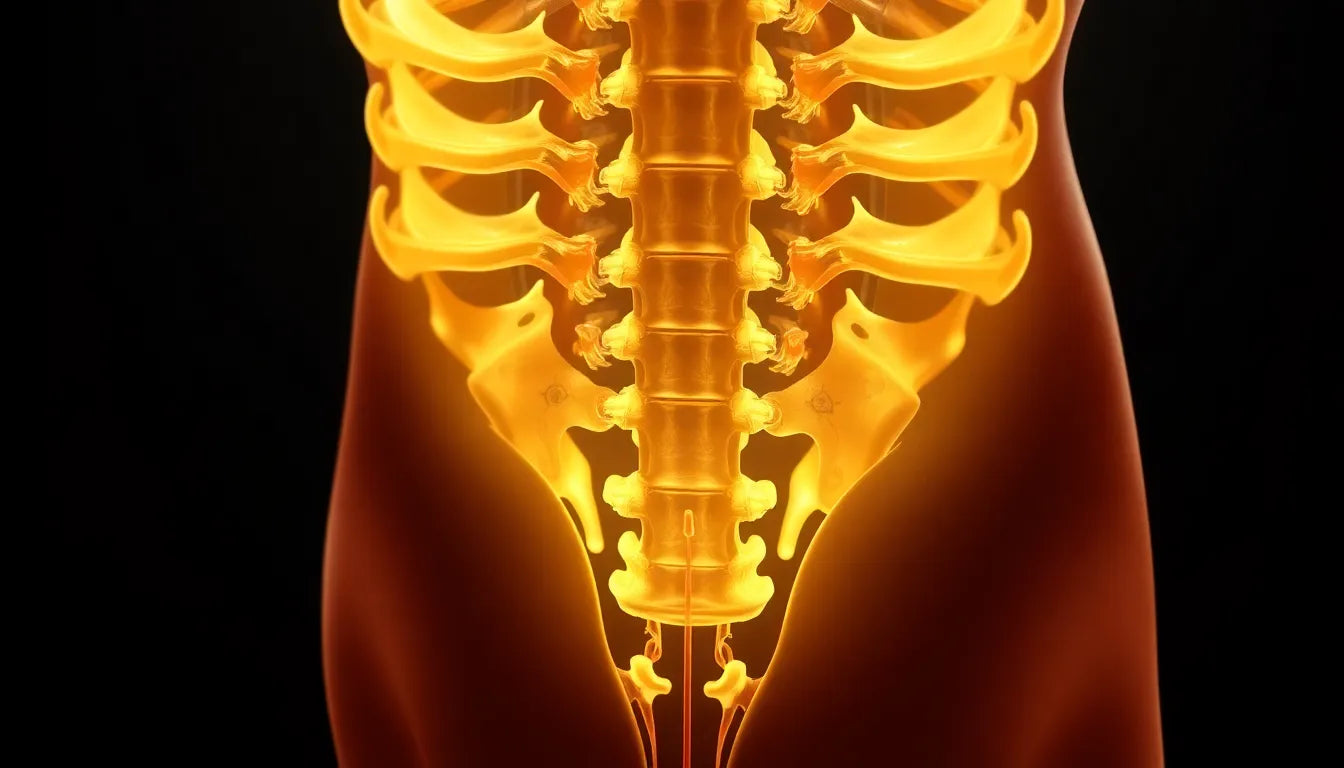

A herniated disc occurs when the soft, gel-like center of a spinal disc pushes through a crack in its tougher exterior. This can irritate nearby nerves and lead to pain, numbness, or weakness in an arm or leg. It's a common condition, particularly among adults aged 30 to 50, and can be caused by various factors, including age-related wear and tear, improper lifting, or even sudden trauma.

The symptoms of a herniated disc can vary widely. Some individuals experience severe pain, while others might only feel a slight discomfort. Common signs include sharp pain radiating down the leg or arm, tingling sensations, and reduced mobility, which can make even the simplest tasks difficult.